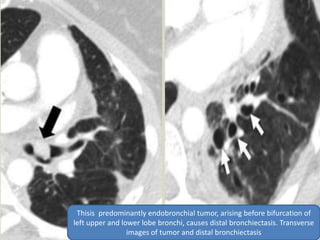

Thisis predominantly endobronchial tumor, arising before bifurcation of

left upper and lower lobe bronchi, causes distal bronchiectasis. Transverse

images of tumor and distal bronchiectasis

 Most carcinoid tumors are primarily

endobronchial lesions, occurring in the central,

main, or segmental bronchi. Some small

tumors are located entirely within the lumen.

However, some display a dominant

extraluminal component with only a small part

of the tumor lying within the airway (iceberg

lesion). A variety of other benign and

malignant neoplasms can also result in

obstruction leading to focal bronchiectasis.